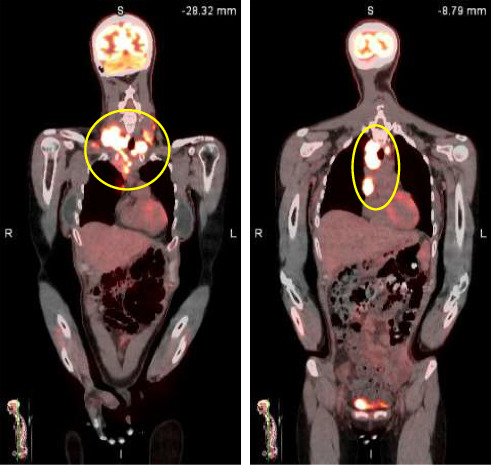

Hodgkin's lymphoma (HL) is uncommon, and its etiology has been attributed to infectious sources such as Epstein-Barr virus (EBV). Though pathogenesis is not completely understood, studies have revealed that specific viral proteins from EBV conduct the process of HL development. In this report, we will discuss the case of a patient who developed EBV-associated classic HL 15 years after an episode of infectious mononucleosis.